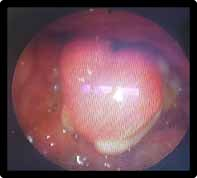

Uvéite Antérieure

Elle se manifeste par une iridocyclite aiguë non granulomateuse, avec un effet Tyndall important dans la chambre antérieure (figure 1), associé dans un 1/3 des cas à un hy- popion composé de polynucléaires neutrophiles (3).